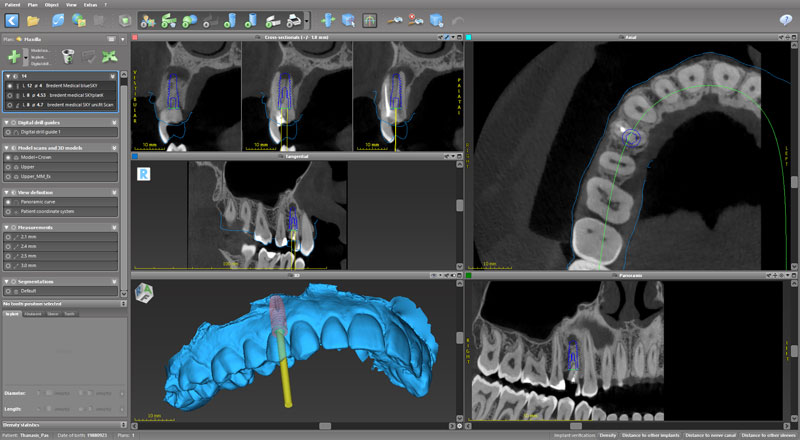

Ψηφιακό πλάνο θεραπείας

Κατευθυνόμενη τοποθέτηση εμφυτευμάτων

Σχεδιασμός χειρουργικού οδηγού

Πρακτική άσκηση: ο κάθε συμμετέχων θα σχεδιάσει σε ειδικό λογισμικό έναν χειρουργικό οδηγό

- Ψηφιακό πλάνο θεραπείας

- Κατευθυνόμενη τοποθέτηση εμφυτευμάτων

- Σχεδιασμός χειρουργικού οδηγού

- Πρακτική άσκηση: ο κάθε συμμετέχων θα σχεδιάσει σε ειδικό λογισμικό έναν χειρουργικό οδηγό